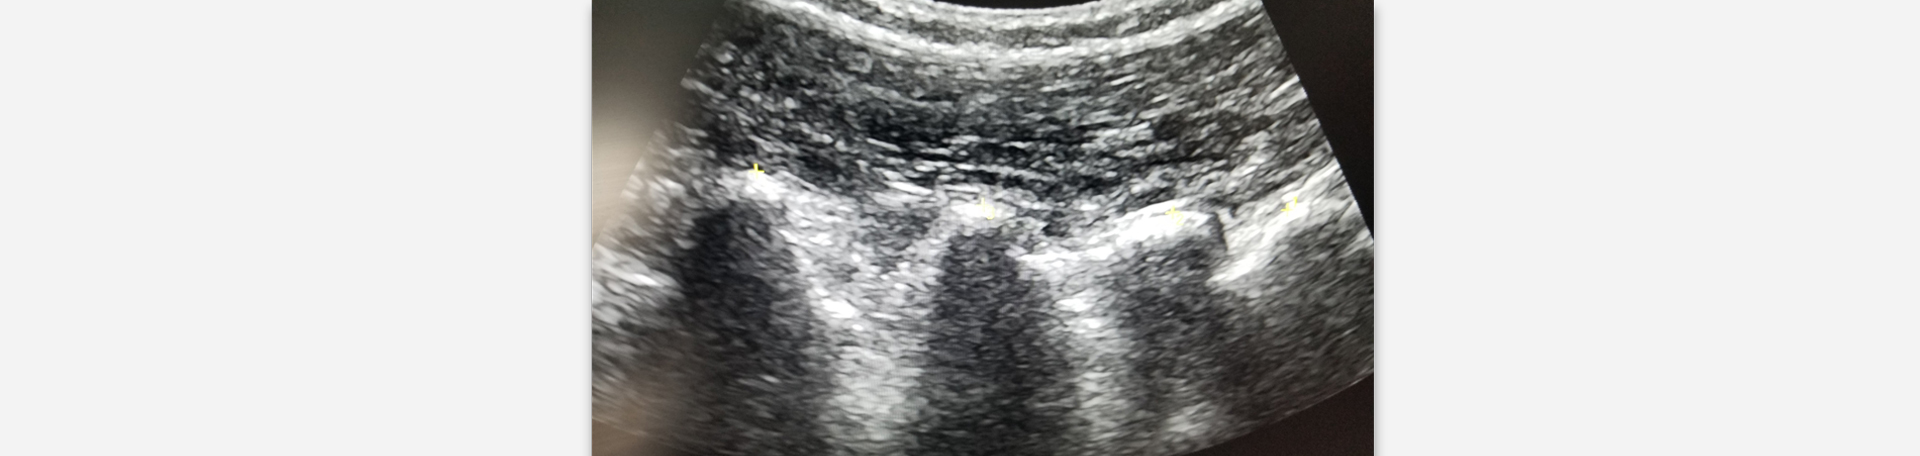

Ever felt like your back was "stuck" or certain movements were just not going to be comfortable? That's just what researchers discovered when they utilized ultrasound technology to see in real time how the spine’s spinous processes moved during flexion distraction treatment. Kruse and colleagues (1) report that this treatment creates very specific, controlled movements of spinal spinous processes where your spine needs help most. Think of it like a skilled mechanic working on a precision instrument. Your chiropractor is not just moving your spine randomly – your chiropractor at Dr. Le's Chiropractic & Wellness, L.L.C. is creating targeted therapeutic motion that addresses the precise spots where you're experiencing issues. For patients dealing with severe pain or those who've had previous back surgeries, this care means getting effective treatment without the concern of overly aggressive treatment.